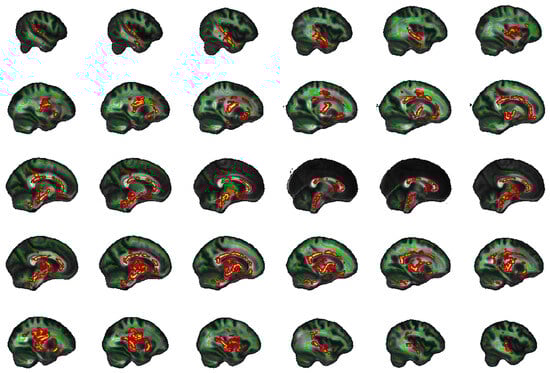

2.5. Exploratory Whole Brain Results

4.8. Exploratory Whole Brain Analysis

| Tracts | Side | Peak Voxel (MNI) | F-Statistic (TFCE) | Cluster Size > 100 (Voxels) | Cluster p-Value | ||

|---|---|---|---|---|---|---|---|

| x | y | z | |||||

| FA | |||||||

| SFOF | Left | −22 | −2 | 19 | 19.5 | 10,610 | 0.001 |

| ILF | Right | 45 | −11 | −27 | 14.2 | 6452 | 0.003 |

| UNC, IFOF | Right | 18 | 24 | −12 | 13.8 | 669 | 0.015 |

| AD | |||||||

| Unclassified | Left | −10 | −1 | −14 | 17.3 | 12,958 | 0.001 |

| ILF | Right | 40 | −22 | −21 | 11.5 | 1739 | 0.014 |

| Forceps minor | Right | 12 | 31 | 8 | 10 | 1522 | 0.028 |

| UNC, IFOF | Right | 28 | 14 | −10 | 9.84 | 786 | 0.03 |

| Unclassified | Right | 1 | 10 | 14 | 7.64 | 188 | 0.047 |

| Forceps minor | Left | −12 | 29 | −12 | 9.1 | 157 | 0.042 |

| SLF | Left | −34 | −37 | 21 | 10.3 | 141 | 0.038 |

| ATR, IFOF | Right | 23 | 26 | 23 | 5.94 | 141 | 0.047 |

| MD | |||||||

| ATR | Left | −11 | −17 | −2 | 18.1 | 31,113 | 0.001 |

| RD | |||||||

| ATR | Left | −23 | −2 | 17 | 18.8 | 14,709 | 0.001 |

| ILF | Right | 45 | −10 | −28 | 15.3 | 6641 | 0.004 |

| UNC, IFOF | Right | 18 | 24 | −12 | 13.4 | 209 | 0.039 |